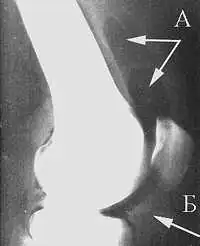

Газовая подушка в верхнем завороте (А); контуры жирового тела (Б) на артропневмограмме коленного сустава

Ранее предлагалось выполнение внутрисуставной оксигенотерапии и озонотерапии. Считалось, что внутрисуставная оксигенотерапия патогенетически обоснована, так как в условиях кислородной недостаточности усиливается гликолиз в тканях сустава, в результате чего накапливаются недоокисленные продукты обмена: молочная, пировиноградные кислоты. Для их окисления требуется усиленная доставка кислорода в ткани сустава. Кроме того, кислород растягивает капсулу сустава и создаёт разгружающую «газовую» подушку[43]. В настоящее время этот метод не используется и не содержится в рекомендациях по данному вопросу[44].